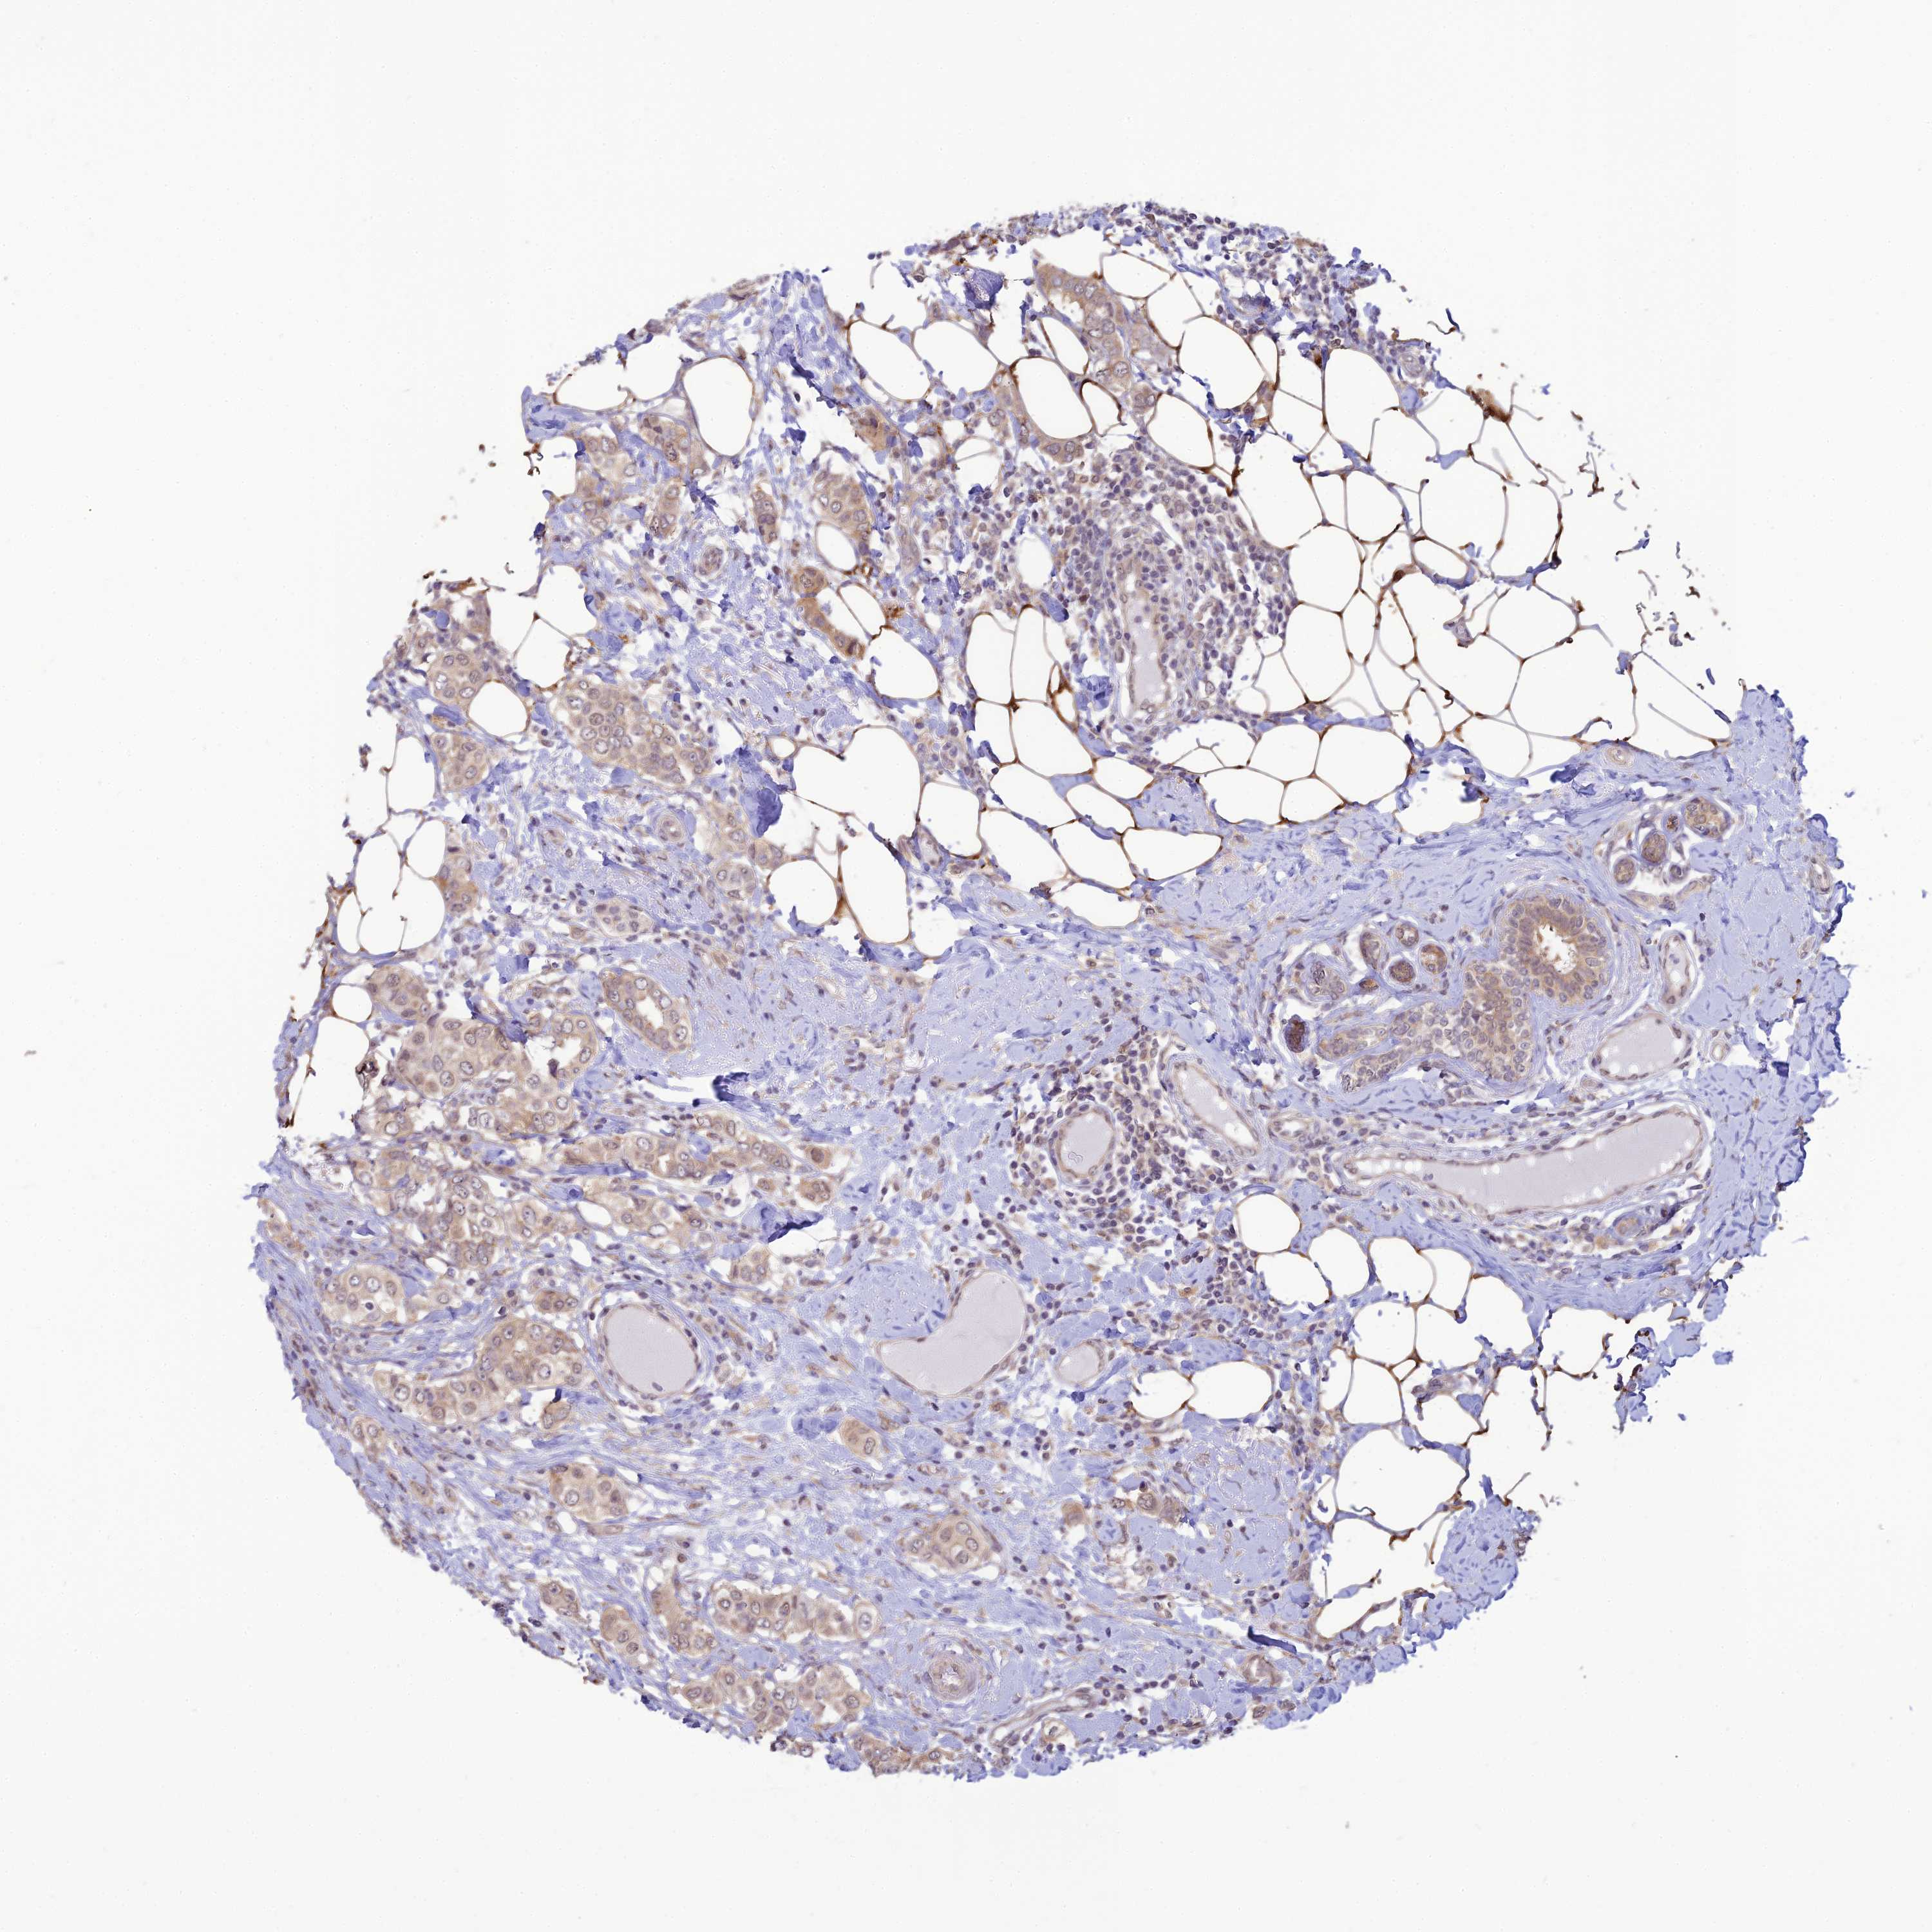

CANCER BREAST CANCER Show tissue menu

BRCA TCGA BRCA VALIDATION PROTEIN EXPRESSION